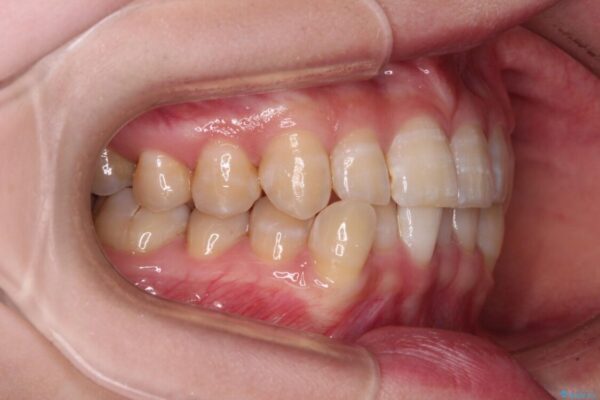

下顎の八重歯を気にして来院された患者様です。

下顎前歯にデコボコが集中していたため、顎間ゴムによる後方移動とIPR(歯と歯の間を削ること)により歯列を整えることとしました。

治療前、下顎前歯のデコボコが集中しており、奥歯の咬み合わせは、上顎に対して下顎が前方位にある状態でした。下顎の歯列を後方へ移動させる治療はインビザラインの得意とするところですので、1年程度で無事に治療を終えることができました。

治療前

• 【モニター】下顎前歯のデコボコをインビザラインできれいに 治療前画像